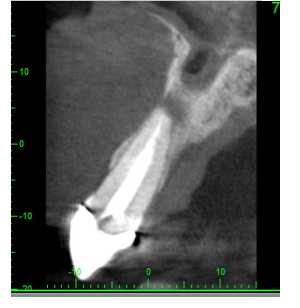

CBCT scan OF UR1 Site, peri-apical cyst?

• Peri-apical lesion UR1 seen on radiograph

• RCT carried out 10 years ago

• Asymptomatic

• No clinical signs

• Is the lesion healing vs active disease?